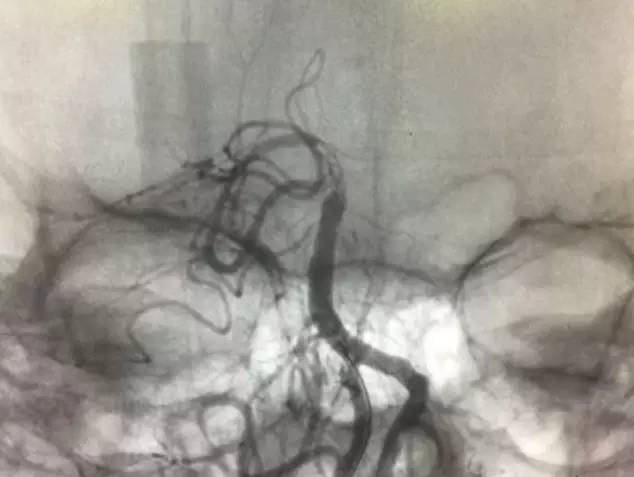

▼右椎动脉造影见基底动脉末端闭塞。双侧颈内动脉造影无殊,双侧后交通未见显影。

通过造影明确病变为基底动脉末端闭塞,机制?

1:左椎动脉急性闭塞同时血栓脱落远端栓塞?

2:左椎动脉是陈旧性闭塞,闭塞末端血栓脱落或者基底动脉原位血栓?

问题焦点是左椎动脉是否是急性闭塞,这直接决定开通策略不同:如果是急性闭塞那么先开通左椎再开通基底,如果不是那么就直接开通基底。根据片子很难准确判断左椎是否是急性闭塞,纠结后决定直接去开通基底:椎动脉长段闭塞而且肌支代偿很好,应该是陈旧性闭塞可能大,尽快开通基底为患者争夺时间。